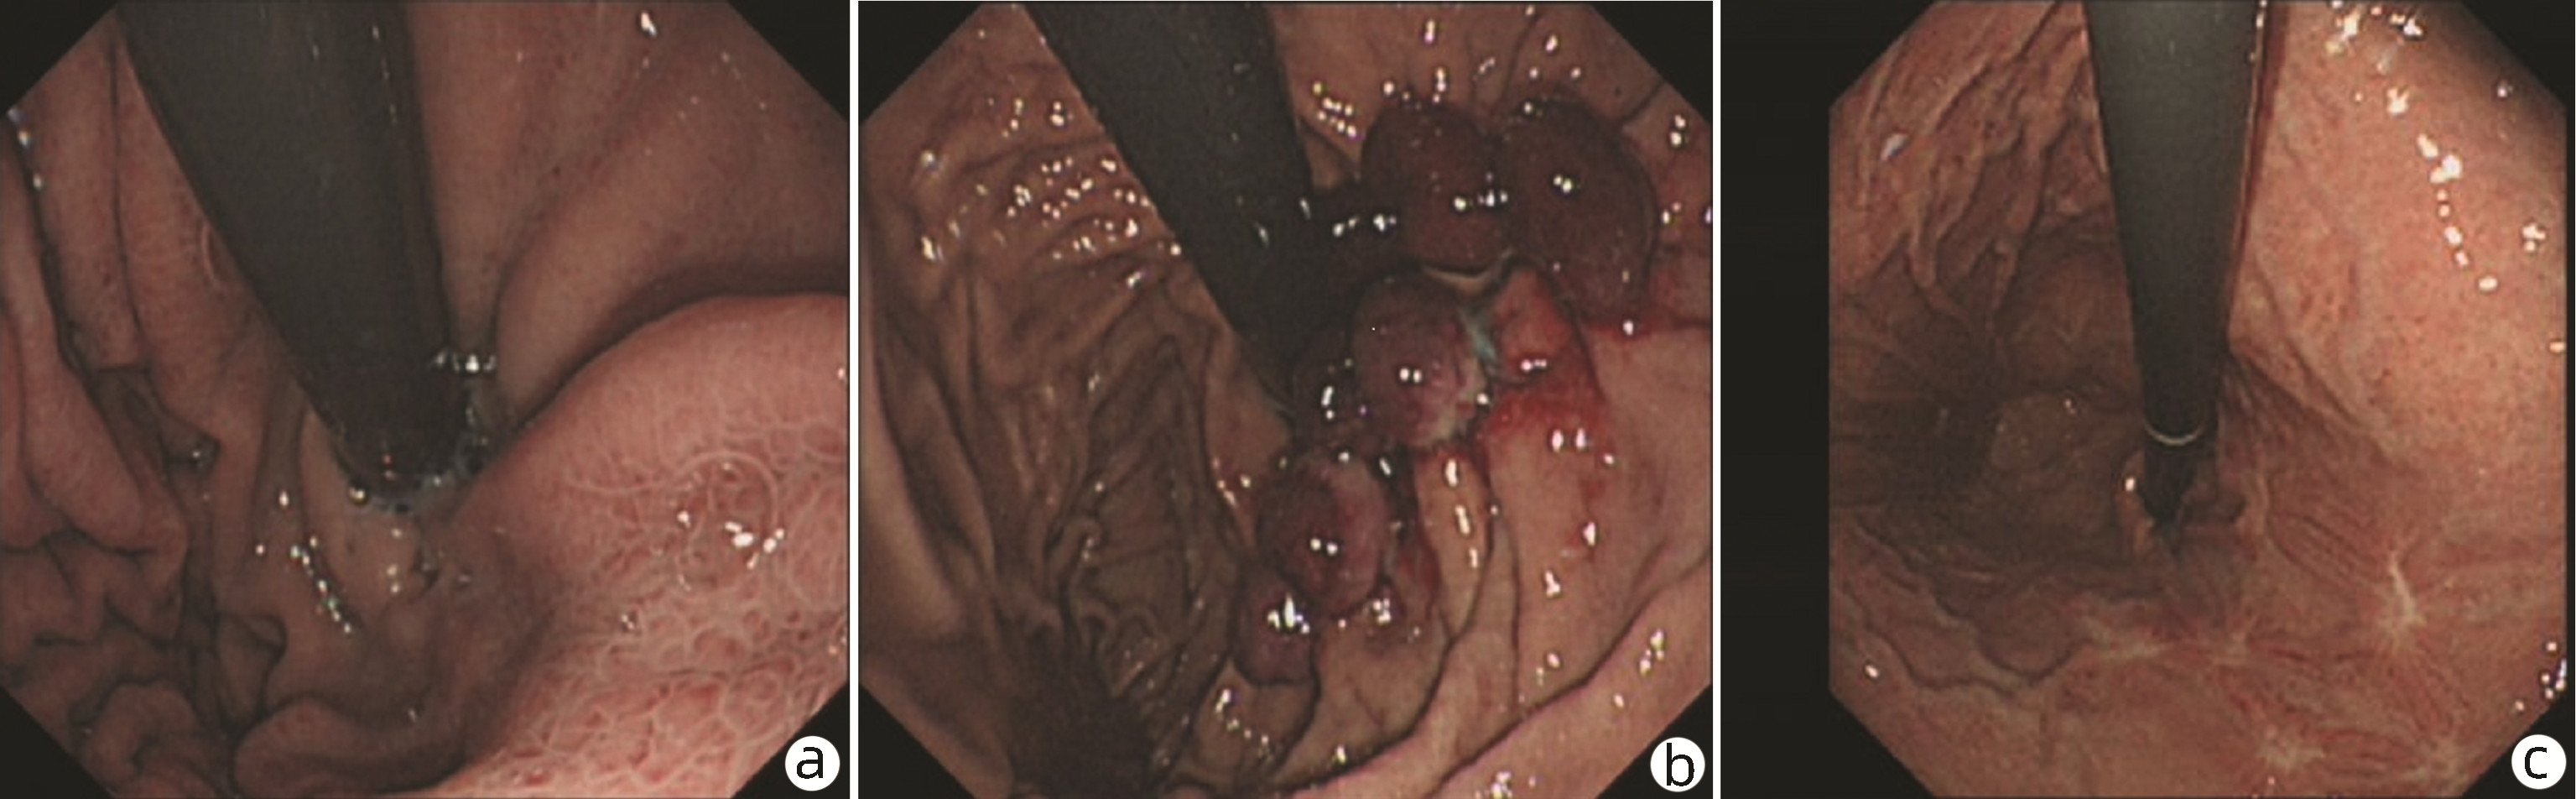

内镜下序贯套扎治疗食管胃伴十二指肠静脉曲张1例报告

文皓, 何朝晖, 蒋彤, 石国庆

2023, 39(3): 637-639. DOI: 10.3969/j.issn.1001-5256.2023.03.024

摘要(891) HTML (275) PDF (2676KB)(111)

摘要: